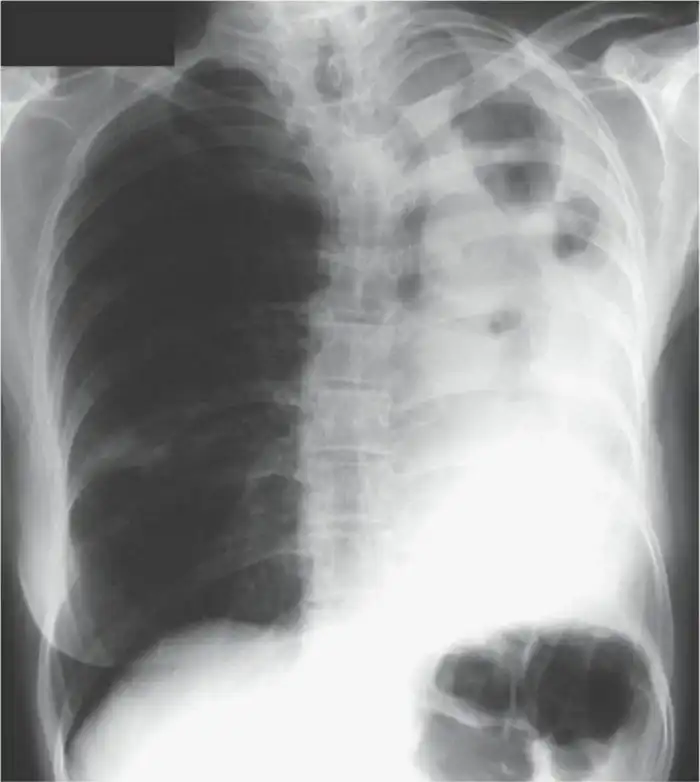

Рентгенограмма большой грибковой опухоли:

Бэтси в итоге спасли, и она успешно перешла от острой формы к хронической, оставшись на этом свете с кашлем, необходимостью постоянного лечения и жутковатым жизненным опытом. В её случае врачи пришли к мнению, что виновником заболевания стала компостная куча на заднем дворе, где у Бэтси был сад. Но так ли всё просто?

“Аспергиллез” лишь общее название весьма нескромной группы болезней, вызываемых грибами рода Aspergillus. В большинстве своем, заболевание наиболее характерно для уже больных или сильно ослабленных людей. Это все, кто перенес или всё ещё болеет самыми разными болезнями, связанными с легкими: от туберкулеза и хронической обструктивной болезни легких до астмы и тяжелых форм аллергий. В случае с Бэтси она обзавелась аспергилломой, проще говоря, в её легких разросся грибной мицелий. Чтобы в бронхе или в легком выросли грибы, недостаточно просто вдохнуть споры плесени. Вы и так это делаете постоянно. Для того, чтобы они прижились, необходимо иметь повреждения (в виде гранулемы, например). И тогда, попав в полость гранулемы, абсцесса или кисты, споры прорастают, и начинает расти аспергиллома.